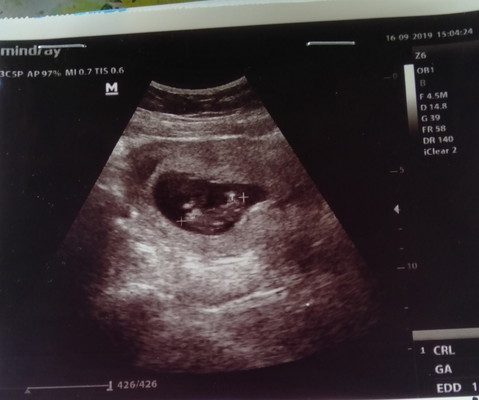

ท้องสอง

ตอนนี้10สัปดาห์เห็นแล้วดิ้นๆท้องสองตื่นเต้นมากค่ะครั้งนี้จะดูแลดีๆละค่ะพลาดมาครั้งหนึ่งจะครบกำหนดคลอดแล้ว แต่น้องเสียในท้อง ตอนนี้น้องกลับมาแล้วค่ะ